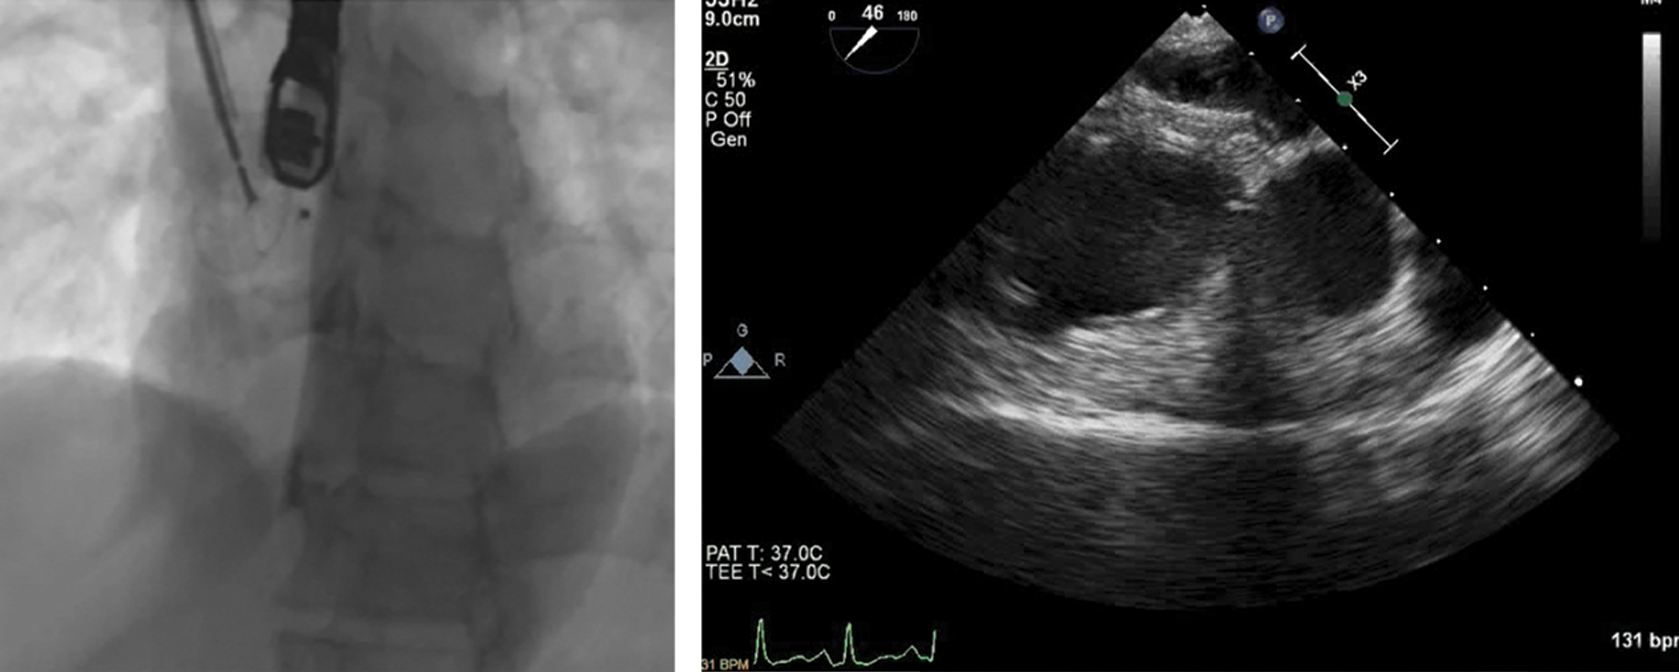

The Heart Team decided to proceed to ASD closure via the right internal jugular vein (IJV) approach. The procedure was performed under general anesthesia and continuous TEE monitoring. After insertion of a femoral artery line for hemodynamic monitoring, a 100-U/kg bolus of heparin was administered. A 6F right IJV sheath access was introduced and a 6 Fr Cobra catheter (Cook Medical) was easily negotiated through the defect, although stable sheath position in the LA could not be maintained. Following, a 9Fr steerable sheath (Fustar Steerable Introducer sheath, Lifetech Scientific, Shenzen) was engaged to advance a 6Fr multipurpose catheter into the LA over a 0.035” 145 cm J-tip guidewire (Bard Medical). However, since a 0.035” stainless steel wire was not supporting sheath passage into the LA, a 0.035” 260 cm Amplatz super-stiff guidewire (Cook Corporation) was exchanged and introduced via the multipurpose catheter. The wire was not maintaining a stable position in any of the pulmonary veins (Fig. 2).

Figure 2: Fluoroscopy (left panel) and transesophageal echocardiography (right panel) images showing the wire in the left atrium through the atrial septal defect, unable to maintain a stable position in the pulmonary veins